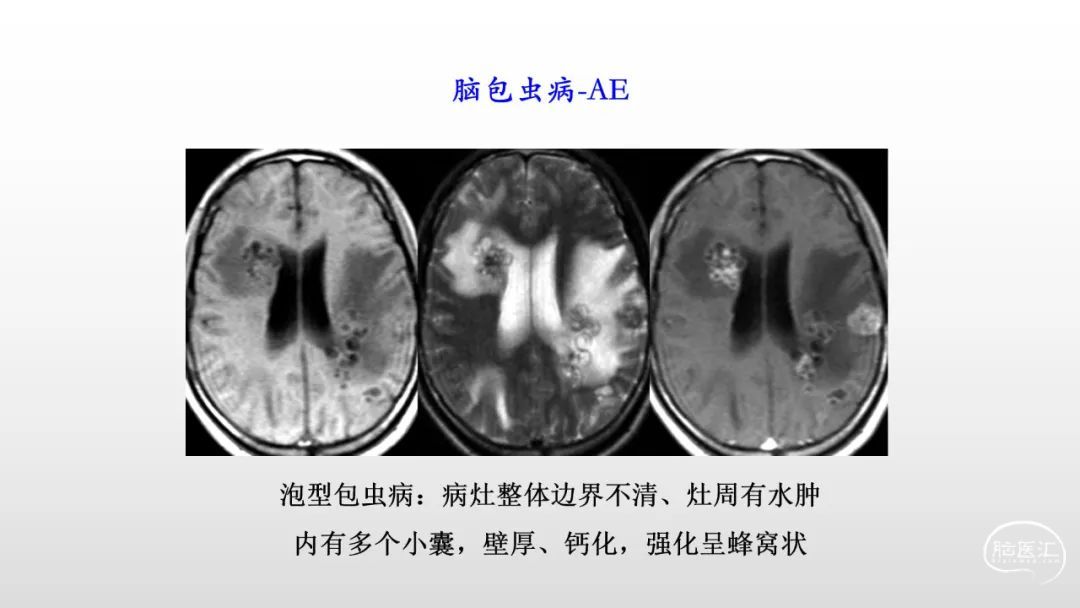

颅脑影像诊断基础知识讲座:感染和免疫性疾病1